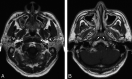

Fig 3.

Axial T1-weighted contrast-enhanced MR image of the nasopharynx in 2 patients with suspected NPC (group 2) where cancer was initially missed by endoscopy and biopsy but identified by MR imaging. Patient with a small cancer in the left fossa of Rosenmuller (arrows) (stage T1) (A) and patient with a small cancer over the torus tubarius (arrows) (stage T1) (B).